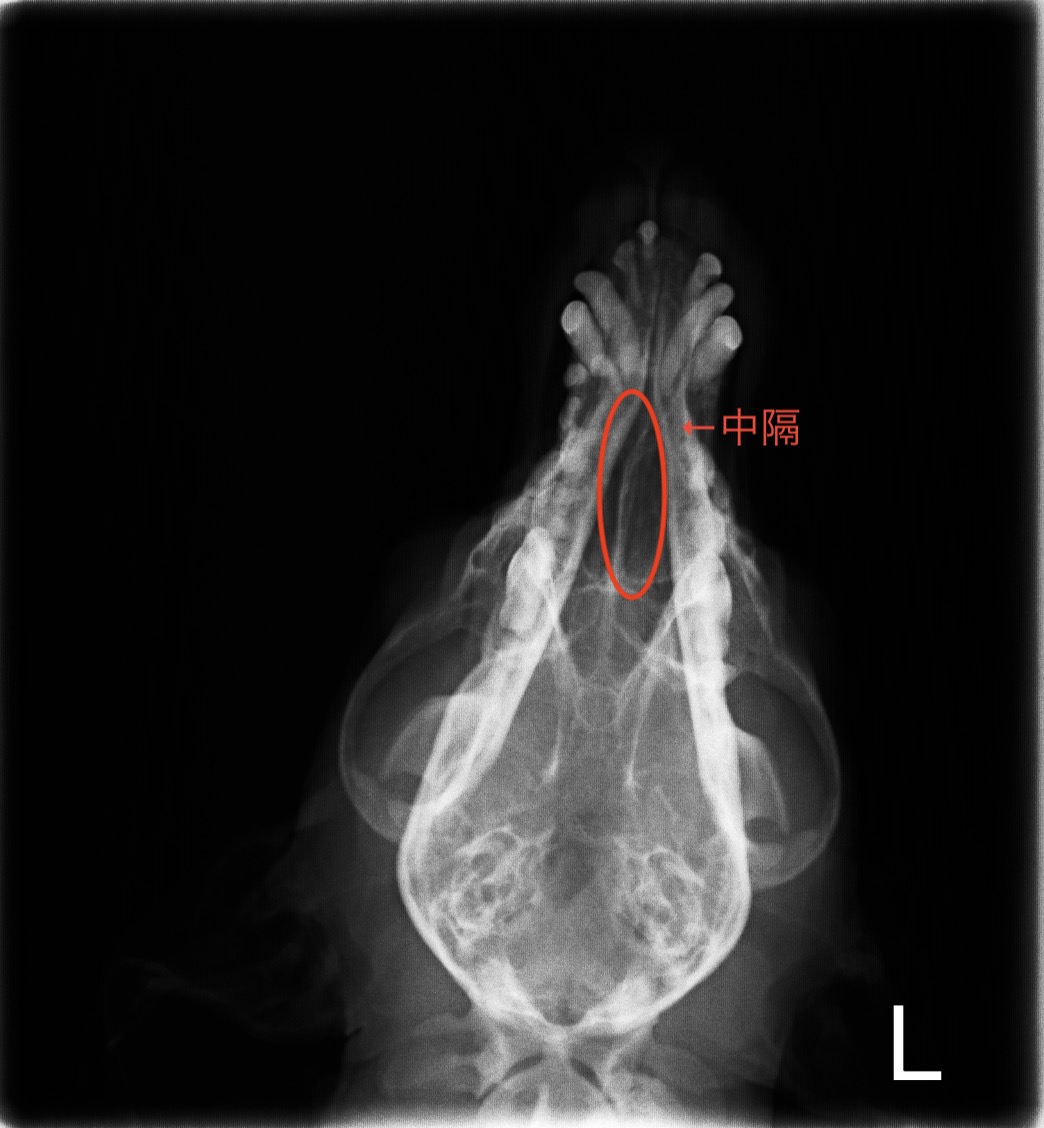

下の画像が院内での鼻部のレントゲン検査の画像です。

左右の鼻腔を隔てている中核が少し右側に圧迫されている様子は認められますが、鼻腔内に明らかな腫瘤は確認できませんでした。